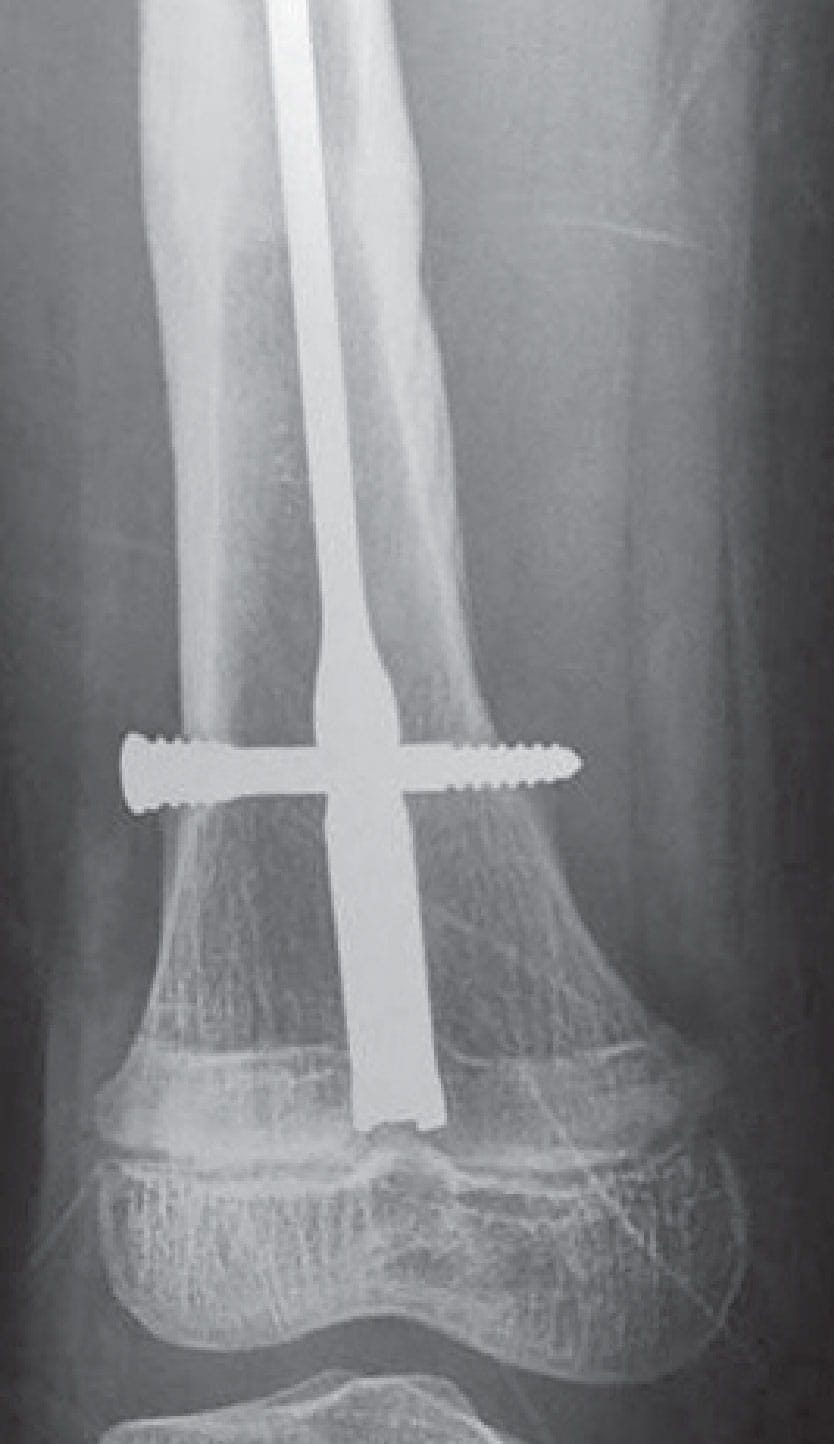

Retrograde femoral nailing involves drilling through the distal femoral physis, the most active lower-extremity growth plate. If that growth plate closes, the child could end up with a severely short or crooked limb. Is it possible, Dr. Liu wondered, to place a large intramedullary nail into this area without damaging the growth plate?

Dr. Liu’s pilot study, published in Journal of Pediatric Orthopaedics, shows it should work under certain conditions. “Our study has demonstrated that the growth plate functions appropriately with a metal rod across it,” Dr. Liu says. “It has also given us parameters to guide the surgeons in these countries in terms of nail sizing and insertion technique.”

Dr. Liu says more research is required before advocating the technique to pediatric surgeons in resource-poor countries. Unlike in the first animal study, a nail placed into a child will change its position relative to the growth plate as the child grows, with the growth plate passing away from the tip of the nail.

However, data from a second sheep study, recently presented at the European Paediatric Orthopaedic Society and Pediatric Orthopaedic Society of North America (POSNA) annual meetings, suggest that growth can slow down after retrograde femoral nailing. Specifically, growth issues are suspect after the growth plate has growth beyond the end of the nail, with microscopic analysis demonstrating small bony bars forming across the growth plate.